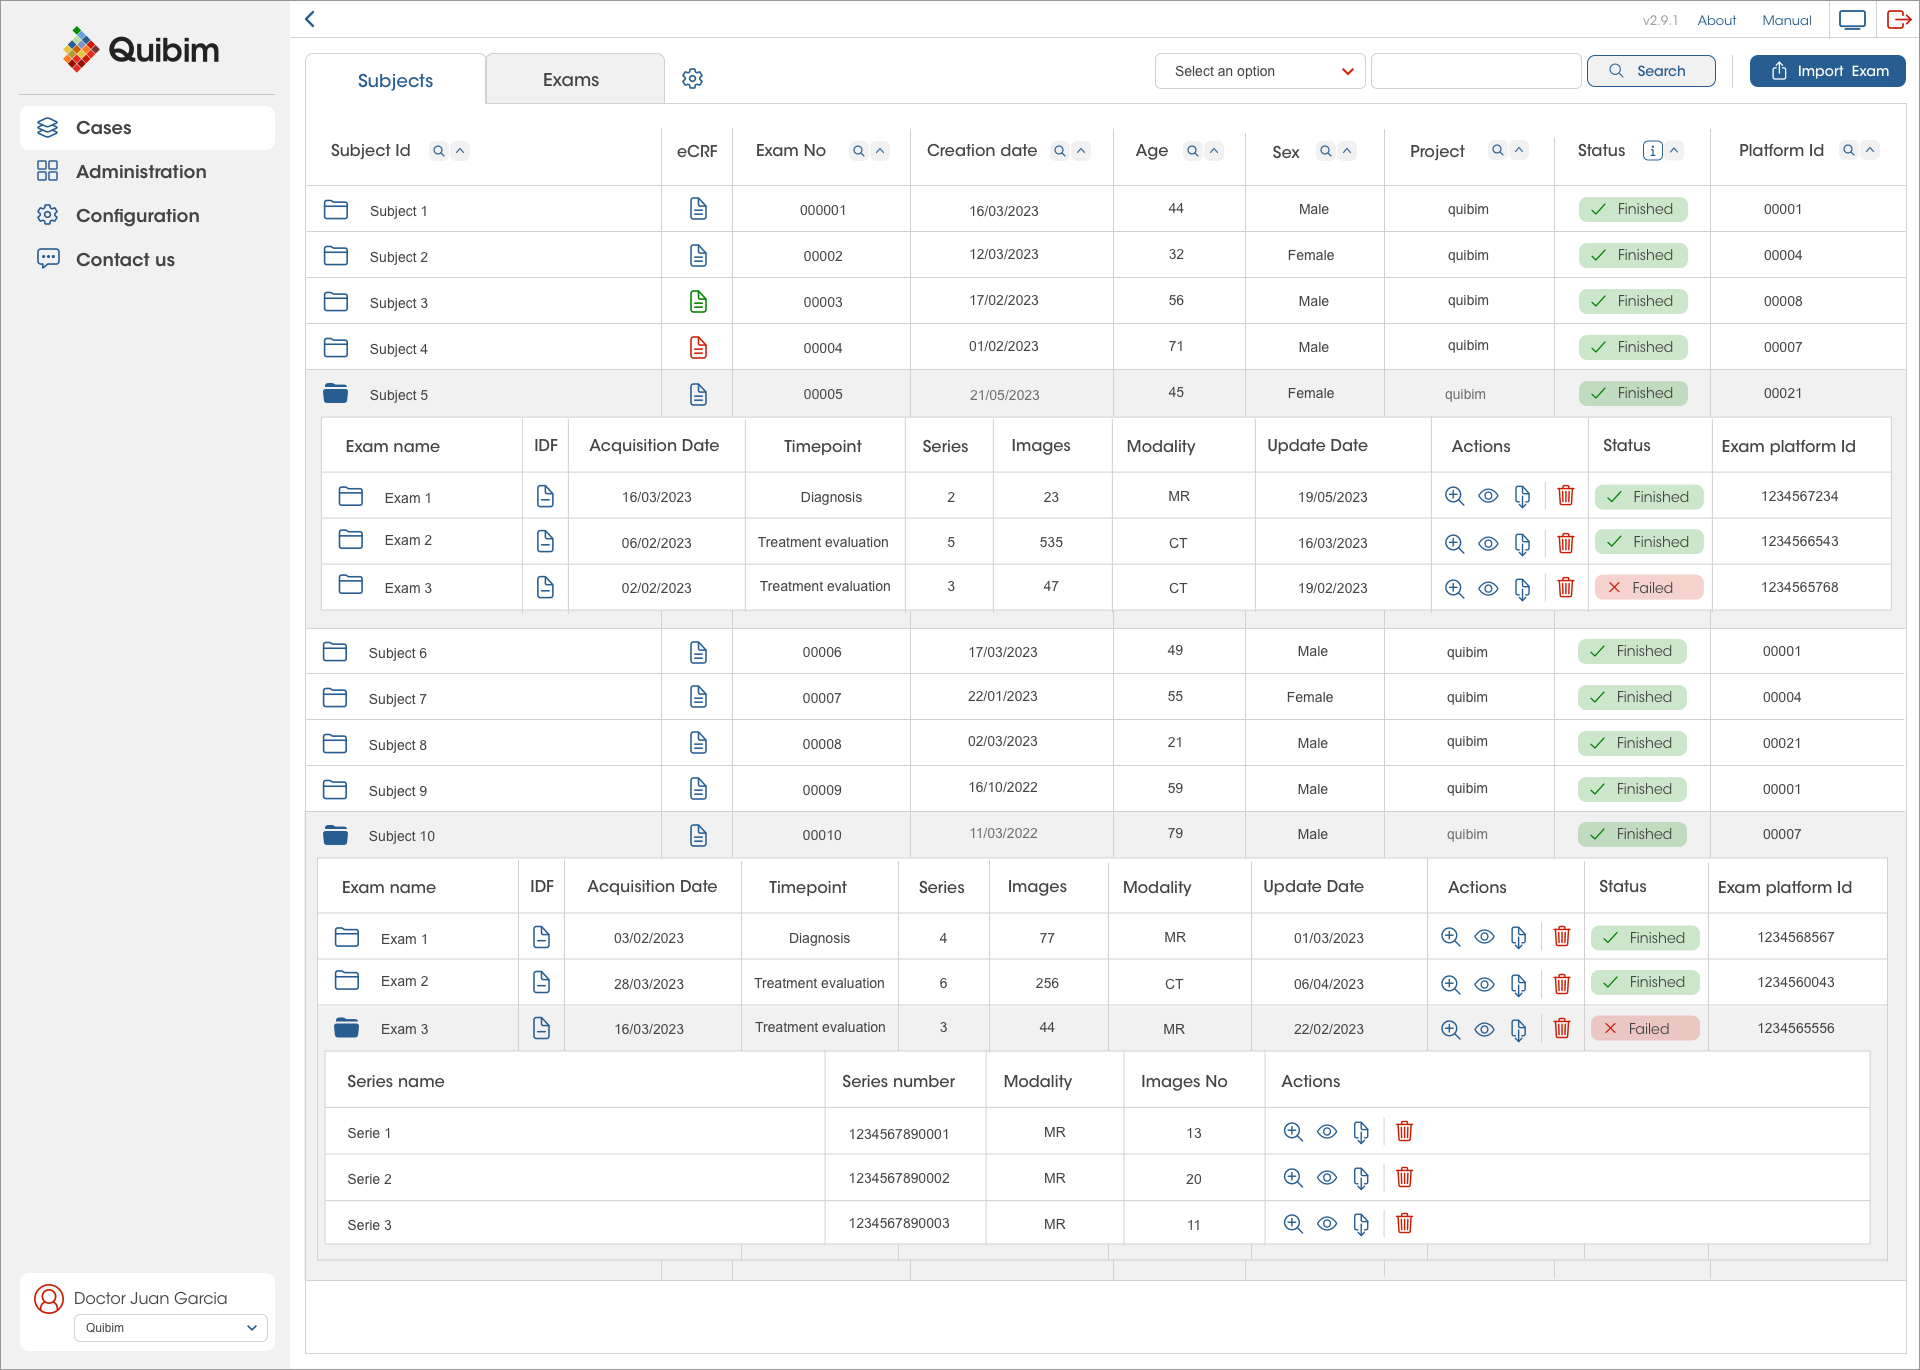

The Multi-Omics Data Management Solution

QP-Insights platform is highly customizable based on the user’s requirements, includes an embedded zero footprint DICOM viewer for radiological readings, semi-automatic treatment response evaluation, AI-driven organ/lesion segmentation and automatic quantification of imaging biomarkers, incorporates electronic case report forms (eCRF) interoperability and a DataMiner tool.

Zero-footprint DICOM viewer

It allows users to load, display, and annotate DICOM files. The annotation tool provides a complete diagnostic aid, allowing users to annotate findings and regions of interest (ROI) and perform organ segmentation with accurate and easy-to-handle tools.

eCRF interoperability

Real-time integration of imaging biomarkers quantification with electronic data capture (EDC) for clinical trials. QP-Insights platform also offers an eCRF customized for each specific clinical study.

Example of an eCRF integrated in QP-Insights for localized prostate cancer